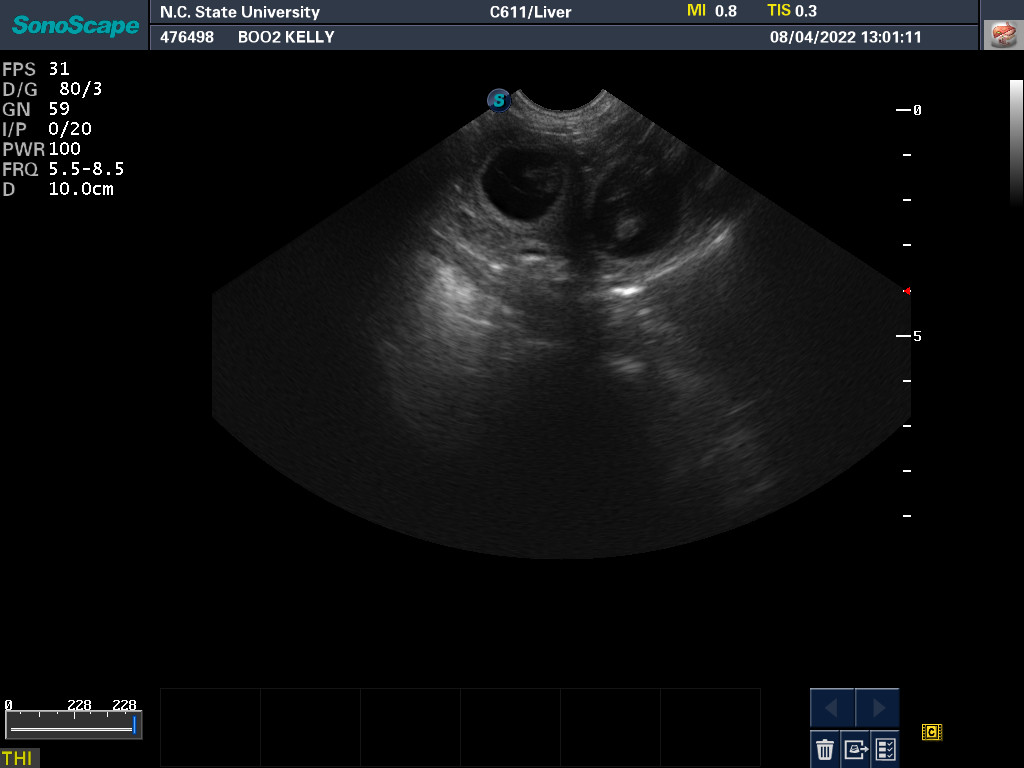

4 Aug 2022

Ultrasound today by the theriogenology (reproduction) veterinarians at NC State University showed that Boo is pregnant with two, possibly three puppies. It is difficult to accurately count puppies using ultrasound.

If all goes well, puppies are due around 5 September.